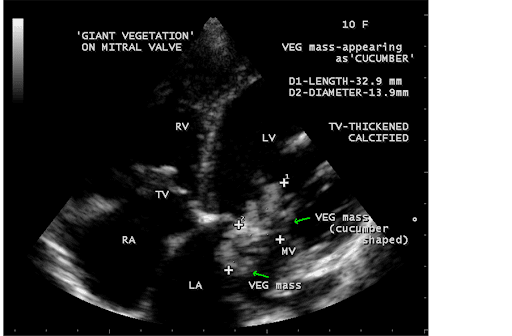

An acute, emergent situation could be caused by mitral valve prolapse or papillary muscle rupture. If severe, valve disease can cause congestive heart failure. The delivery system includes a tapered tip to facilitate crossing of the native valve. Panel a shows the gross appearance of a large vegetation on a rheumatic mitral valve, as measured in centimeters. A cardiac mass can be diagnosed by echocardiography (ekg) and other imaging tests like echo doppler, mri and ct scans.